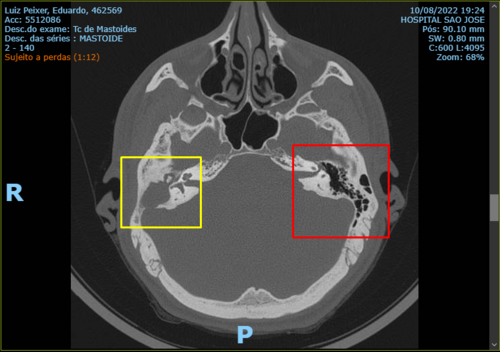

Tomografia Realizada

O quadrado vermelho mostra o meu ouvido esquerdo, que seria como um ouvido normal deveria ser, a parte preta é o ar que se encontra dentro de ouvido.

O quadrado amarelo é o meu ouvido direito, o que se encontra com o colesteatoma, como a tomografia mostra ele não se encontra com ar dentro dele, pois é ali que o colesteatoma está, o cisto já cresceu por todo o osso do meu ouvido.